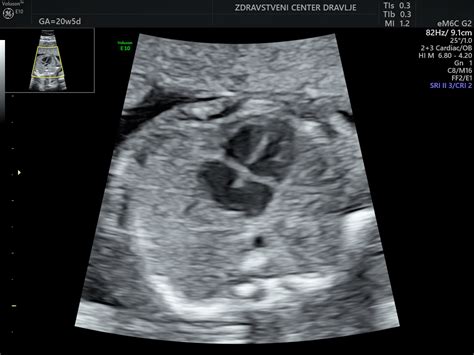

Šesti mesec nosečnosti, ki obsega približno 22. do 26. teden, je čas, ko plod že dobro napreduje v razvoju. V tem obdobju se njegovi notranji organi že nahajajo na svojih mestih, čeprav se bodo še naprej razvijali in dozorevali. Sluh ploda je že tako razvit, da lahko reagira na glasne zvoke, in že prepoznava mamin glas. Koža postaja manj prosojna in pridobiva rožnato-rdečo barvo zaradi nastajanja pigmenta. V pljučih se začne proizvajati surfaktant, snov, ki omogoča, da se zračni mehurčki napolnijo z zrakom brez zlepljenja. Telo nosečnice se še naprej prilagaja na naraščajočo težo in velikost ploda. Maternica sega že nad popkom, kar lahko povzroča pritisk na želodec in zgago. Zaradi povečane količine krvi in hormonskih sprememb lahko nosečnica občuti hitrejše bitje srca in pogostejše uriniranje. Lasje postanejo močnejši in gostejši, nohti pa trdi in močni.